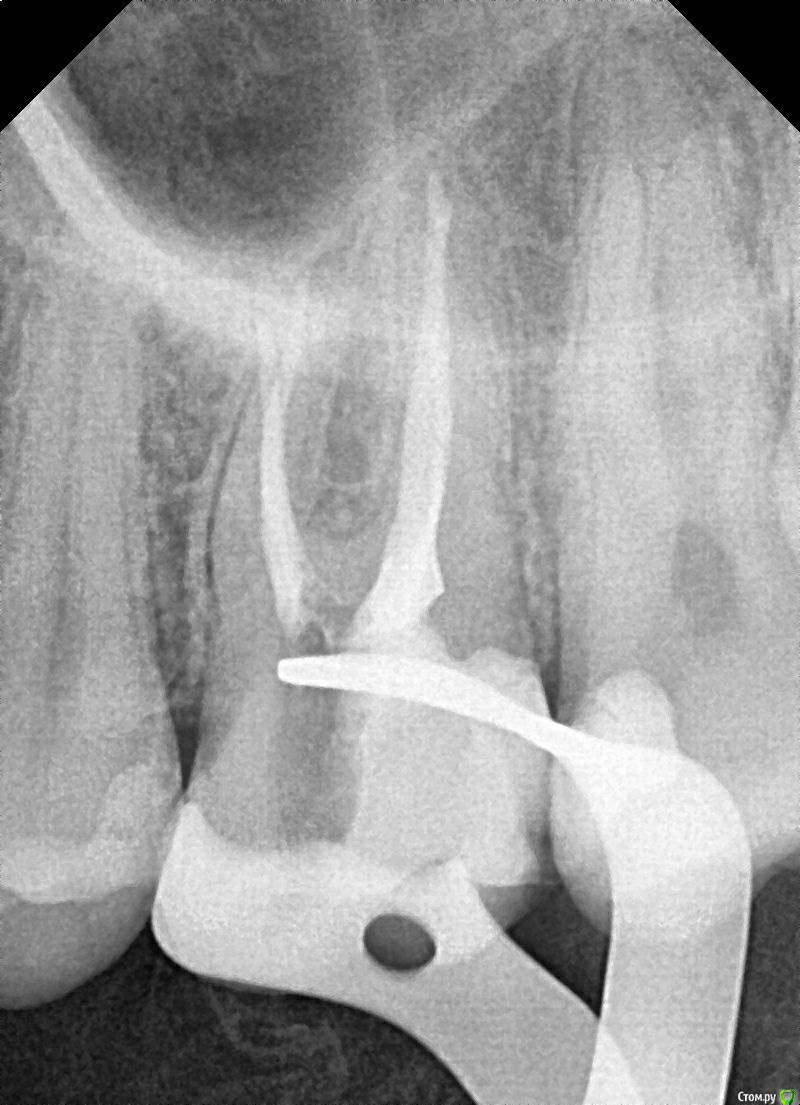

Liza544 Опубликовано 3 февраля, 2020 Поделиться Опубликовано 3 февраля, 2020 Добрый день.Помогите, пожалуйста, разобраться с причиной боли.Началось все приблизительно в начале октября (3 мес назад). Обратилась к стоматологу на проф осмотр, в ходе которого у меня обнаружили пульпит в 26-м зубе. В результате - удалили 3 нерва, но, со временем я обнаружила, что боль не прошла. Обходила несколько клиник. В ходе этого сделала пломбу на соседнем 25-м зубе. Совсем недавно удалила в том же 26-м зубе 4-й "маленький" нерв, так как сначала его не удалили, потому что не заметили (удаляла в клинике без микроскопа).В итоге, боль осталась прежней. Боль в области состыковки 26-го и 25-го зубов (при прикусывании на эту область). Наиболее логичными и вероятными предположениями, как по мне, являются: 1) 28-й зуб (зуб мудрости) , который у меня не удален - давит на соседние зубы и вызывает данную боль. Но, почему тогда, не болит 27-й? хотя, когда между 27 и 26-м провожу ниткой - есть кровь. 2) Воспалена десна. Один из стоматологов выразил данное предположение и в принципе оно может иметь место, так как когда вожу ниткой между 26-м и 25-м - болит десна. Но почему тогда так же болит и при надкусывании? К тому же, если в 26-м нету нервов, так как их удалили, как он вообще может болеть? Непонятно... Прилагаю снимки 25, 26, 27 и зуба мудрости.Буду очень признательна за хоть какие-нибудь предположения и комментарии. Спасибо. Ссылка на комментарий

Liza544 Опубликовано 4 февраля, 2020 Автор Поделиться Опубликовано 4 февраля, 2020 Вот еще пару снимков которые у меня есть. ПРошу заметить, что последние 4 снимка (файлы 7-10), которые я тут прикрепила - до пломбы на 25-м зубе и до залеченного 4-го канала в 26-м зубе. Подскажите пожалуйста, может ли быть зуб недостаточно залечен, хотя на КТ ничего подозрительного не видно? Ссылка на комментарий

ЛанаМ Опубликовано 4 февраля, 2020 Поделиться Опубликовано 4 февраля, 2020 Воспаление десны может давать постоянные ноющие боли и боль при накусывании. От чистки сразу не пройдет, нужно дней 5-7 противоспалительного лечения и отсутствие травмирования (постараться ниткой не чистить). Также нужно убедиться, что нет хронического воспаления в гайморовой пазухе. Побольше срезов кт, желательно уже после пломбирования четвертого канала. Да, бывают проблемы в зубе и при идеальной картинке рентгеновского снимка. На нем видны только крупные каналы, а там еще целая сеть мелких. Ссылка на комментарий